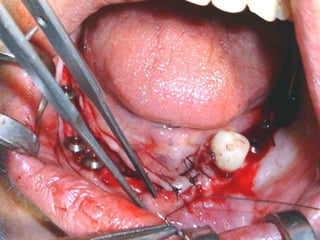

Estructura en íntimocontacto con la superficie ósea, quedando los postes fuera de la fibromucosa gingival..

Sutura de colgajosque cubren la estructura, dejando los postes bien visibles.

Colocación de laprótesis dentaria.

Estructura implantada pordebajo del periostio:

• Los implantessubperiósticos son parte de la historia de la Odontología, sin embargo en su momento fueron una buena solución para casos protésicos difíciles.